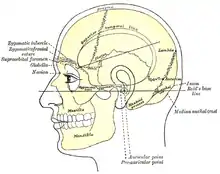

Side view of head, showing surface relations of bones. (Mastoid process labeled near center.)